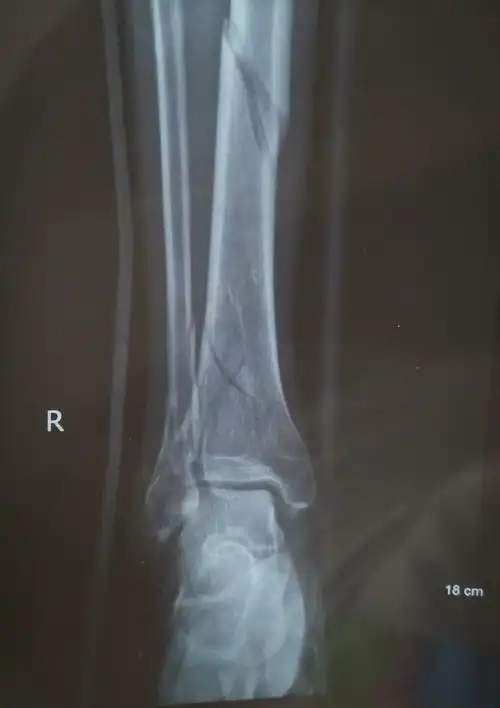

典型踝关节骨折的治疗讨论

脚踝左腓骨远端骨折月记

三周前,我从高处跳下,伤到了脚踝,请您帮我看看x光片,看是哪里骨折了?

甘肃省人民医院骨一科杨青山副主任医师团队:踝关节骨折

胫骨骨折伴踝关节骨折手术分享